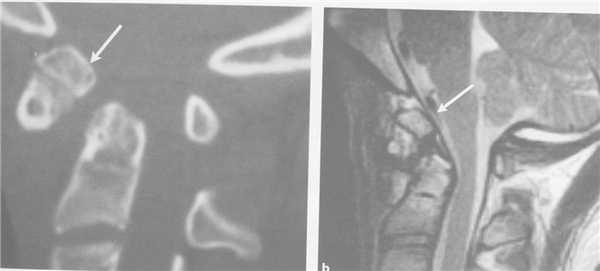

КТ является методом выбора для оценки костного повреждения. Однако более полную информацию о состоянии спинного мозга даёт МРТ.

КТ. Перелом тела С2 (красные стрелки).

Особую категорию составляют пациенты, у которых, несмотря на наличие неврологической симптоматики, не выявляется изменений при рентгенографии или КТ. Число таких пациентов составляет около 10%. Среди различных механизмов подобных травм наиболее вероятна кратковременная компрессия спинного мозга задней продольной связкой и дисками, либо, жёлтой связкой и пластиной дуги. Посколько резкие сгибания и разгибания наблюдаются при высокой подвижности в сегментах, такие травмы более вероятны в шейном отделе позвоночника. Спондилолиз усугубляет эту ситуацию, приводя к центральному синдрому спинного мозга. В этих случаях необходимой является МРТ позвоночника. Характерными находками, которые мы часто видим при травмах при МРТ в СПб, являются отёк спинного мозга и гематома, причём последняя при МРТ позвоночника плохим прогностическим фактором в отношении восстановления неврологического дефицита. К наиболее тяжелым осложнениям шейной травмы относится расслоение магистральных артерий, определяемое по МРТ, МРА или КТ и КТА. В высоком поле такой вид травм лучше виден чем в открытом МРТ. МРТ СПб позволяет выбирать место МРТ, однако, острая травма шейного отдела позвоночника требует высокоспециализированного нейрохирургического отделения

МРТ шейного отдела позвоночника. Острая травма. Компрессия спинного мозга, отек и контузия. Сагиттальная Т2-взвешенная МРТ.